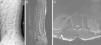

(A–C) A 21-year-old man with atypical spinal TB. (A) Lateral thoracic vertebra radiograph showed irregular lesions at the T7–10 vertebral body. (B), (C) MRI showed slight lesions at the upper and lower edges of T7–10 vertebral body. L3 vertebral body accessories had high signal on T2-weighted images. (D–F) A 45-year-old man with atypical spinal TB. (D) MRI showed multiple abscesses in extradural intraspinal canal at C1-T3 without identifiable osseous lesion. (E), (F) MRI showed multiple paravertebral abscesses at L1-S2 without identifiable osseous lesion.